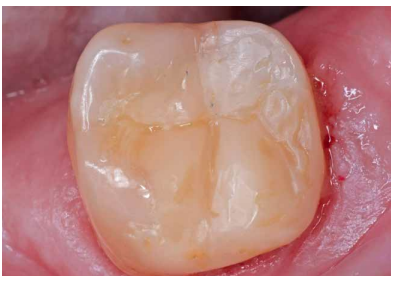

Por último, se realizó la restauración encofrando el diente con una matriz Automatrix (Dentsply Sirona; York, Pensilvania, EE. UU.) (Figura 6). Se grabó el esmalte de forma selectiva con ácido ortofosfórico 37% (Total Etch, Ivoclar Vivadent; Liechtenstein) y se aplicó adhesivo autograba dor de dos pasos Clearfil SE Bond 2 (Kuraray; Tokio, Japón), como indica el fabricante. Se colocó composite Filtek Supreme XTE A3,5 Body (3M Oral Care; Minnesota, EE. UU.) con técnica incremental polimerizando 40 segundos cada capa con la lámpara Polylux II (Kavo; Biberach, Baden-Wurtemberg, Alemania). Se retiró la matriz, el aislamiento y se ajustó la oclusión. Se eliminaron los excesos en distal con una hoja de bisturí número 12 y se pulió la restauración con el sistema PoGo (Dentsply Sirona; York, Pensilvania, EE. UU.) (Figuras 7 y 8).

Se realizaron revisiones a 1 mes, 6 y 18 meses (Figuras 9 y 10), observando en la última radiografía de control mejoría en la lesión apical de la raíz distal. En todas las revisiones, la paciente se encontraba asintomática, la prueba de sensibilidad al frío fue fisiológica, al igual que la prueba de palpación, percusión y de mordida. El sondaje y la movilidad continuaban fisiológicos.